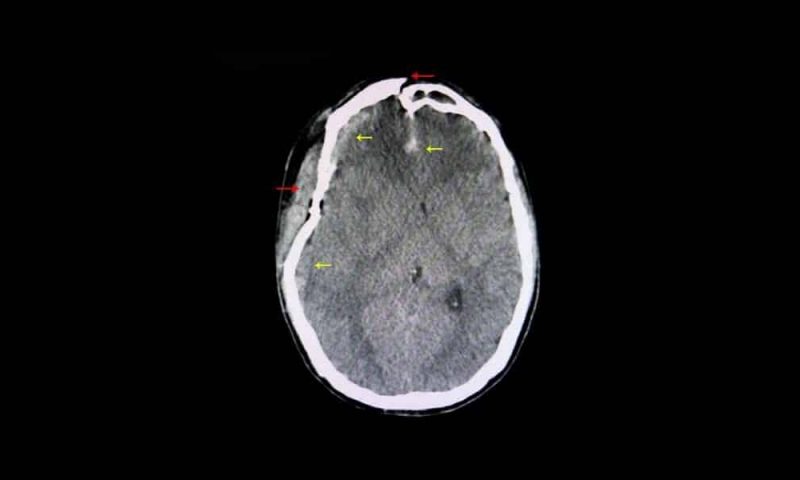

The brain can experience movement inside the skull so suddenly that it hits both inside walls. In other words, both sides of the brain are injured. This is incredibly dangerous. It’s a major cause of brain swelling after a car accident and can even lead to bleeding in the brain itself. There may be skull fractures associated with it. A crash in which the car rolls over is a likely cause of this injury.